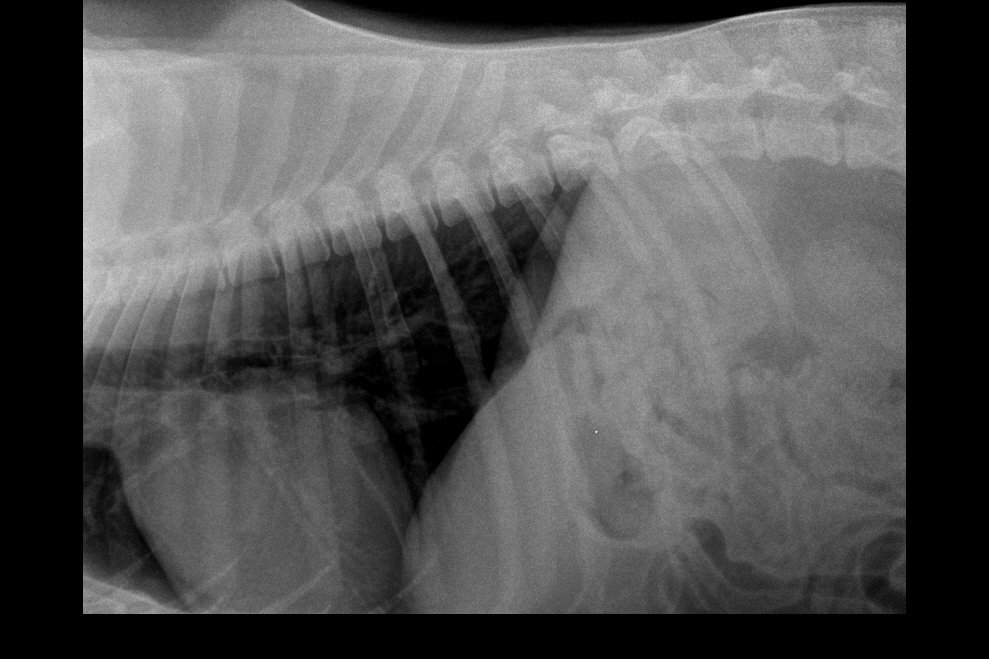

Garret Posted March 14, 2019 Share Posted March 14, 2019 Hi Guys, My dog has been diagnosed with IVDD since February 2nd of 2019. Im at a lost to treat him, please help. So far Im taking him for acupuncture 2x a week. He is being medicated with Analsik 2x a day, and I apply Glucosamine Gel over his joints. Since he has a hard time walking I'm trying to learn to express bladder him, but pooping is still something I can't figure out how to help him does it. So far my vet has diagnosed him with IVDD from looking at his Xray. But there is something that me and my doctor are not sure about which is the Xray on his neck, regarding what is near the AXIS of his neck. I don't know where to ask to next.. I have consulted with 5 vets and not one of them seems to be able to give a definite answer. Some say its a piece of the fracture that broke off, other speculate that it might be cancer. I'm really scared for my dog, and if anyone could help tell me more on what exactly is happening to my dog's neck. or at least point me where I could better ask these questions would help a lot! Link to comment Share on other sites More sharing options...